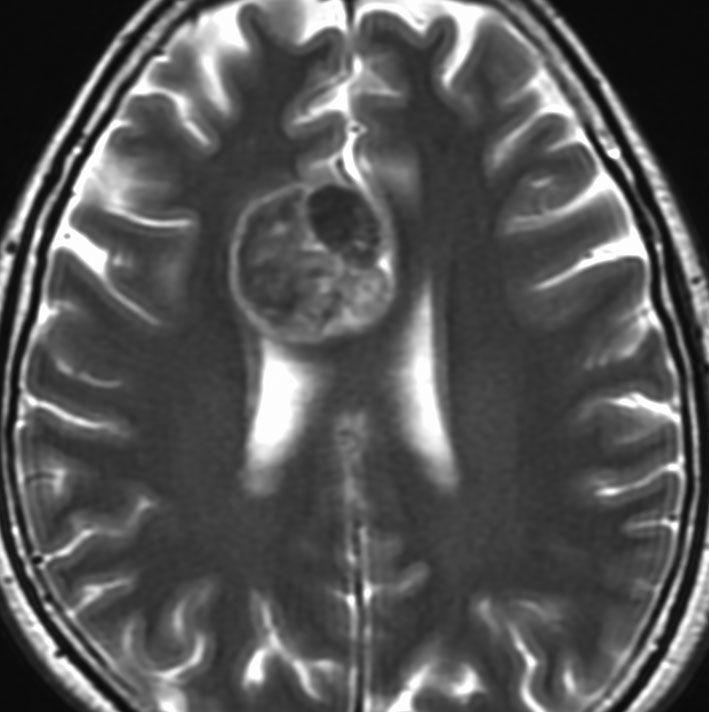

膵臓がんの脳転移 症状 診断 治療 余命および特徴的な遺伝子異常と